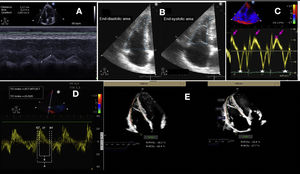

A. TAPSE. B. FAC. C. Tissue Doppler. The arrow indicates the systolic wave and the star indicates the velocity of the e wave. D. TEI index: measures the ratio between the isovolumetric contraction and relaxation times in relation to systolic ejection. It can be quantified with pulsed Doppler or from the tissue Doppler registry. The advantage of tissue Doppler is that it can record all the information of the cardiac cycle in the same beat, and improves the reproducibility of the technique. Measurement is made of the isovolumetric contraction time (ICT), the isovolumetric relaxation time (IRT) and the ejection time (ET) in the pulsed tissue Doppler spectrum of the lateral tricuspid annulus. E. Strain.

TAPSE (tricuspid annular plane systolic excursion). This parameter represents a measure of longitudinal function. It is determined in the apical 4C plane with the cursor optimally aligned in the lateral tricuspid annulus, and measures the degree of longitudinal displacement of the annular segment of the RV from end-diastole to the systolic peak. It is not particularly dependent upon good image quality. The TAPSE has a prognostic value in PHT,31 and a value of < 17 mm suggests systolic dysfunction of the RV.24 The parameter has limitations in post-heart surgery patients (Fig. 3A).

FAC (fractional area change). This parameter estimates global ventricular function. It is quantified in the apical 4C plane through tracing of the end-diastolic (EDA) and end-systolic area (ESA) of the RV, taking care to include the trabeculae in the cavity. Formula: (EDA-ESA)/EDA x 100, values < 35% indicate systolic dysfunction.24 The FAC is an independent predictor of heart failure, sudden death, stroke and mortality in patients with PTE.32 Compared with TAPSE, the FAC is more precise in estimating systolic function, taking MRI as reference33 (Fig. 3B).

Doppler tissue imaging (DTI). Systolic pulse wave velocity (Sʹ). This parameter is obtained in the apical 4C plane using DTI, placing the cursor of the pulsed-wave (PW) Doppler at the middle portion of the basal segment of the lateral tricuspid annulus. It measures the longitudinal velocity. Although the parameter physiologically decreases with age, a value < 9.5 cm/s is considered to be abnormal24 (Fig. 3C).

Right ventricle index of myocardial performance (RIMP) or Tei index. This is an index of the global performance of the RV. The isovolumetric contraction time (IVCT), isovolumetric relaxation time (IVRT) and ejection time (ET) should be measured from the same heartbeat using PW or DTI in the lateral tricuspid annulus. It is important to ensure that the non-consecutive beats have similar RR intervals. The index may be underestimated under conditions of high RA pressures, which will shorten IVRT. A RIMP > 0.43 via PW and > 0.54 via DTI indicates dysfunction of the RV24 (Fig. 3D).

Strain/strain rate tissue deformation image. The data obtained from the DTI study can be used to determine the degree of myocardial deformation of the free wall (strain) and the velocity of myocardial deformation (strain rate). Strain and strain rate estimate the global and regional systolic function of the RV, respectively. Strain is defined as the percentage of systolic shortening of the free wall of the RV from the base to the apex, while strain rate is the velocity with which such shortening takes place.24 Both parameters offer a good correlation with myocardial contractility,34 though strain is less influenced by heart motion and is therefore considered to be more reliable – though it is dependent upon the loading conditions. The strain values should be measured from the apical 4C window without angulation and with high-quality imaging since reverberation and artifacts can affect the placement of the reference points and cause their quantification to be underestimated. The reference points should be limited to the myocardial free wall excluding the pericardium, which may prove difficult since the free wall of the RV is usually thin. A value > –20% is considered normal24 (Fig. 3E).